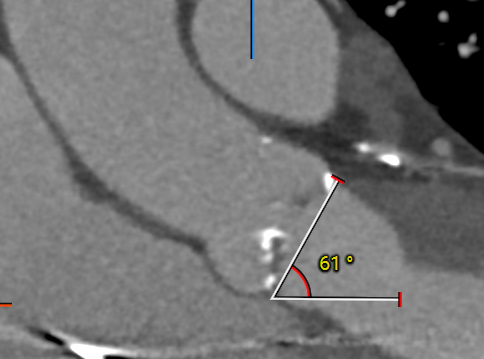

2.主动脉瓣环与水平夹角61°,横位心